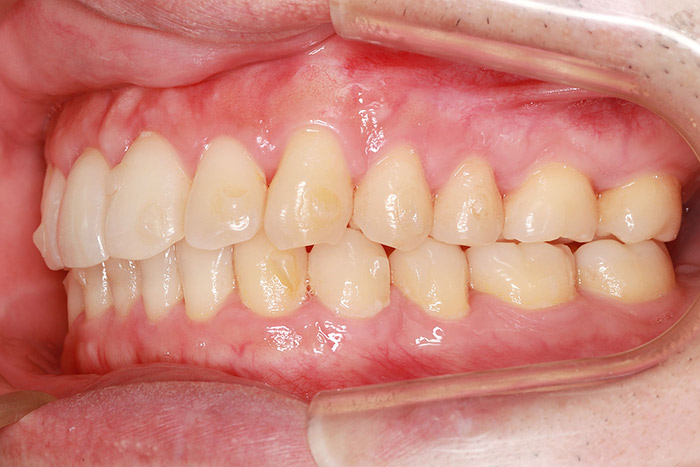

T様

治療前

before

年齢 28歳

性別 女性

治療名称 唇側ブラケット装置(ワイヤー矯正)

総額治療費用 880,000円(税込10%) 金額備考 精密検査料・診断料 33,000円(税込10%)

治療期間 2年6か月 通院頻度など 1か月ごと

患者の症状 叢生、上下顎前突

治療方法 上下顎小臼歯の4本抜歯して唇側マルチブラケット装置にて矯正

治療結果 叢生の解消、口元の突出感も緩和され咬み合わせが良くなりました。

※治療結果は患者様によって個人差があります。

その他治療に関する情報 装置撤去までの通院回数は23回、その後の保定期間(2年間)は3か月に1度の通院。

リスク/副作用 治療前に親知らずの抜歯が必要な場合があります。